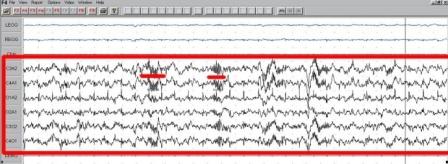

Slika 6: REM-faza. EEG-snimke su izdvojene crvenim pravokutnikom, a pokreti očiju su podcrtani